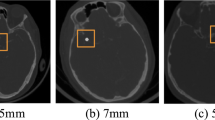

Flat panel computer tomography image data was acquired using a Philips AlluraXper (10 ml contrast agent, Imerson 400, Dilution: 50%). The spatial resolution for the FPCT sequences was 0.185 × 0.185 mm with a temporal resolution of 25 FPS. During the experiments, the valve was triggered with a frequency of 1 Hz, resembling a physiologically plausible heart rate. The pressure of the pump was varied to produce anatomically plausible deformations for the different flow phantom structures. For planning purposes, the deformation was estimated analytically (for calculations see supplemental materials S1). Given the results of previous work (in vivo and in vitro experiments9,12,17), we generated pulsatile deformation of the flow phantom structures in the range of 0.08 to 0.25 mm.

To investigate the feasibility of accurate quantification of geometric deformation of the vessel wall using typical image resolution of different imaging modalities also applied in the given context (e.g. MRI, CT), our high-resolution FPCT imaging data was resampled. In detail, we resampled the FPCT data to an isotropic spatial resolution of 0.37, 0.74 and 1.48 mm/px. Moreover, the original temporal resolution of 25 FPS was reduced to 4 FPS, 2 FPS and 1.5 FPS to cover typical CT, MRI and FPCT literature values. Especially sampling frequencies around 2 FPS are interesting. Given the original dynamic process with an underlying frequency of 1 Hz, it is to be expected that around and especially below this frequency, the reconstruction of the original signal is no longer reliable. This relates to the Nyquist-Shannon sampling theorem21, which states that the sampling rate should be larger than twice the highest frequency component of the original signal.

For evaluation of the deformation quantification performance in the presence of reduced FPCT image resolution, we focussed on a structure with comparably high deformation (fusiform aneurysm, feeding vessel inner diameter of 4 mm) and applied the registration parameters that led to minimal errors during the original resolution experiments.

The results of the deformation estimation accuracy evaluation using the downsampled FPCT data are depicted in Fig. 5. Deformation estimation was executed applying the described registration-based approach and using the optimal parameters as determined in the previous section (gradient step: 1, total field variance: 3). Examining the spatially downsampled data at full temporal resolution, the expected effect of a decreasing accuracy with increasing pixel spacing can be observed. The full-resolution video data reveals a maximum structure expansion of around 0.25 mm (red line) with respect to the minimum expansion state. This value can still be approximately extracted using the 0.37 mm/px and 0.74 mm/px resolution. However, at 1.48 mm/px, the maximum deformation magnitude is estimated to be ca. 0.33 mm, which amounts to a 32% overestimation and, hence, a not reliable deformation estimation.